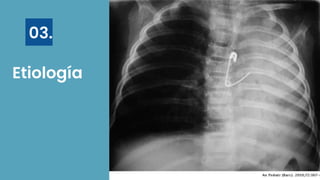

Etiología

03.

Obstructiva No obstructiva